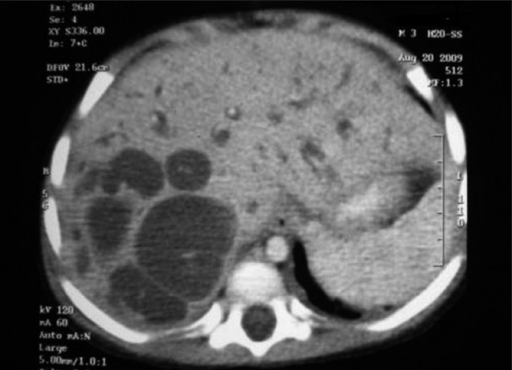

Diagnóza sa odvíja jednak na základe nižšie uvedených príznakov, ale aj na základe zobrazovacích vyšetrení, ako je ultrazvuk, CT či MR. Ďalej sa môžu robiť invazívne vyšetrenia, ako je ERCP.